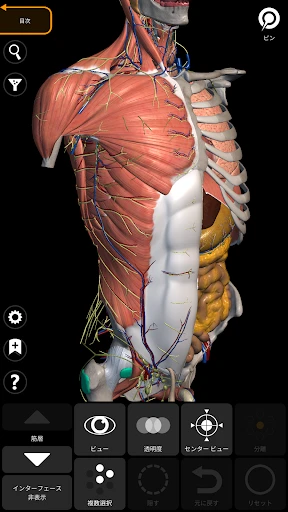

3Dアトラスの驚きの体験

皆さん、3Dで人体を探検したことはありますか?このアプリを使うと、まるで本物の標本を手に取っているかのように、人体の構造を詳細に観察できます。何よりも嬉しいのは、非常にリアルなグラフィックスです。3Dモデルはとても精密で、筋肉や骨、内臓の位置関係が一目瞭然です。

さて、ここで気になるのは使いやすさですよね。ご安心ください!インターフェースは直感的で、スムーズに操作できます。ピンチでズームイン・アウトしたり、スワイプで回転させたりと、直感的なジェスチャーで操作可能です。このあたりは、スマホやタブレットでの操作に慣れている方なら、すぐに使いこなせるはずです。